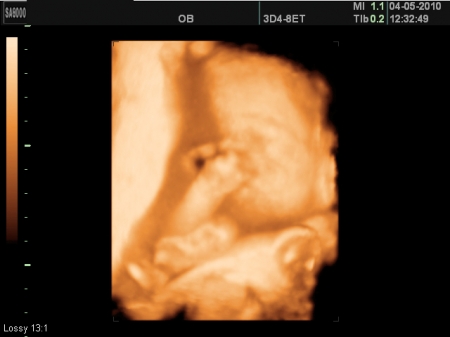

4. Jak vypadá miminko 24. týden těhotenství?

Délka plodu od temene k zadečku je ve 24. týdnu těhotenství asi 21 cm, váha průměrně kolem 530 g.

Plod starý 22 týdnů (24. týden těhotenství). Plod se vznáší v plodové vodě, je obalen plodovými obaly. Děložní dutina již zcela vymizela, sliznice srostla s amniochoriovou blánou. Pupečníkem je plod připojen k placentě. V děložním hrdle je hlenová zátka.